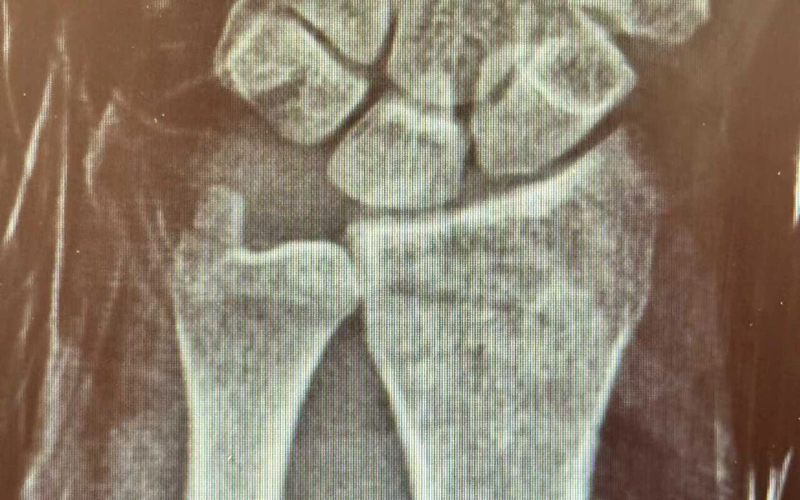

骨外科:无影灯下,为生命“守岁”的工匠

对于骨外科而言,春节假期往往是意外伤害的高发期。为了能让患者尽早解除痛苦、早日回家团圆,骨外科的团队选择了与患者为伴。

农历正月初五,当大家还在走亲访友时,骨外科医生李刚已完成了两例摔伤患者的救治工作。“大过年的,能早一点救治就早一点救治,让他们好好过年。”这是李刚医生朴素的心声,也是全体骨科医护人员的承诺。无影灯下,他们专注的眼神是对生命最大的尊重。

洗菜摔伤治疗前后对比

厕所摔伤治疗前后对比